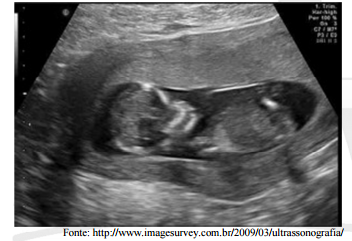

A imagem a seguir retrata um exemplo de ultrassonografia: